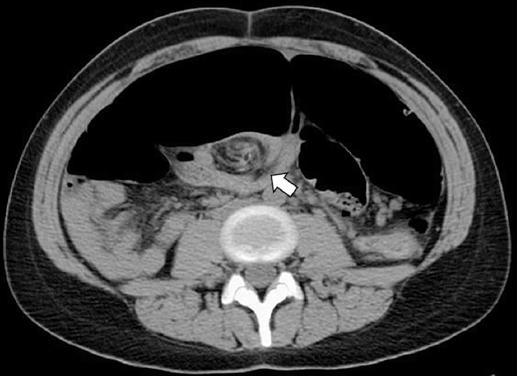

Se realizan estudios de laboratorio, incluyendo biometría hemática completa, pruebas de función renal y hepática, electrolitos séricos, tiempos de coagulación y gasometría arterial, reportándose leucocitosis con neutrofilia (23 × 103/μl, 90% neutrófilos), así como datos de acidosis metabólica y lesión renal aguda incipiente. Una radiografía de abdomen en bipedestación a su ingreso muestra importante dilatación del colon, de hasta 20 cm en su diámetro máximo, con imagen en «grano de café» (Fig. 1). Se realiza tomografía computarizada de abdomen y pelvis, la cual constata una importante dilatación del colon transverso, descendente y sigmoides, con alteraciones del mesenterio (Fig. 2).

Figura 2 Tomografía simple de abdomen, corte axial a nivel de la cicatriz umbilical, documentando el sitio de torsión del eje vascular de vasos mesentéricos, también conocido como «signo del remolino» (flecha).